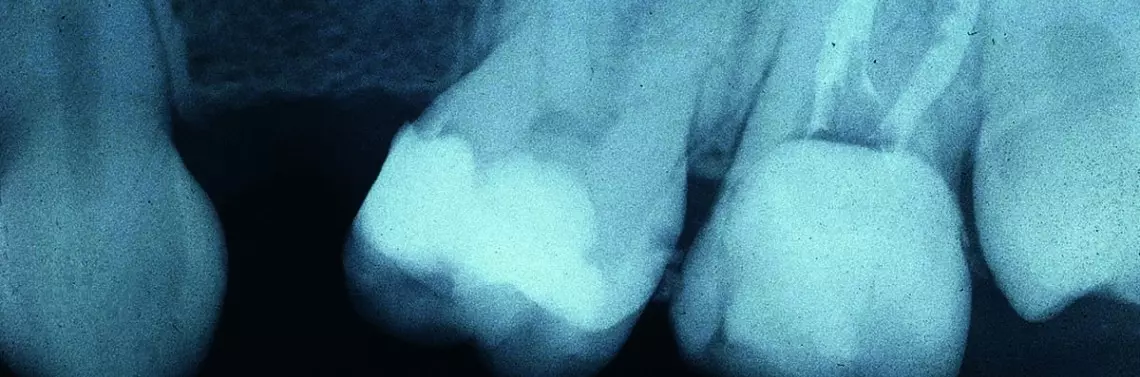

Istotą leczenia kanałowego jest oczyszczenie, dezynfekcja i szczelne wypełnienie systemu kanałów korzeniowych. Dlaczego posługuję się określeniem „system kanałowy”, a nie „kanały”? Dlatego, że stopień skomplikowania budowy przestrzeni endodontycznej waha się od prostego do bardzo skomplikowanego, co przedstawiają poniższe ryciny (zdj. 1–3).

Tak skomplikowana morfologia kanałów korzeniowych nietraktowana w odpowiedni sposób będzie rezerwuarem dla bakterii i resztek miazgi, co przyczyni się do pogorszenia rokowania. Przy odpowiedniej filozofii, z pomocą doświadczenia i sprzętu, wypełnienie takich zawiłości przestrzeni endodontycznej jest jednak możliwe, i to z całkiem dobrym rezultatem. Gojenie zmian, nawet rozległych, stanie się możliwe, a te, które nie poddają się gojeniu, nie są równoznaczne z usunięciem zęba, gdyż zawsze można posiłkować się zabiegami z zakresu mikrochirurgii endodontycznej, które zwiększają szanse na pozostawienie zęba w jamie ustnej.